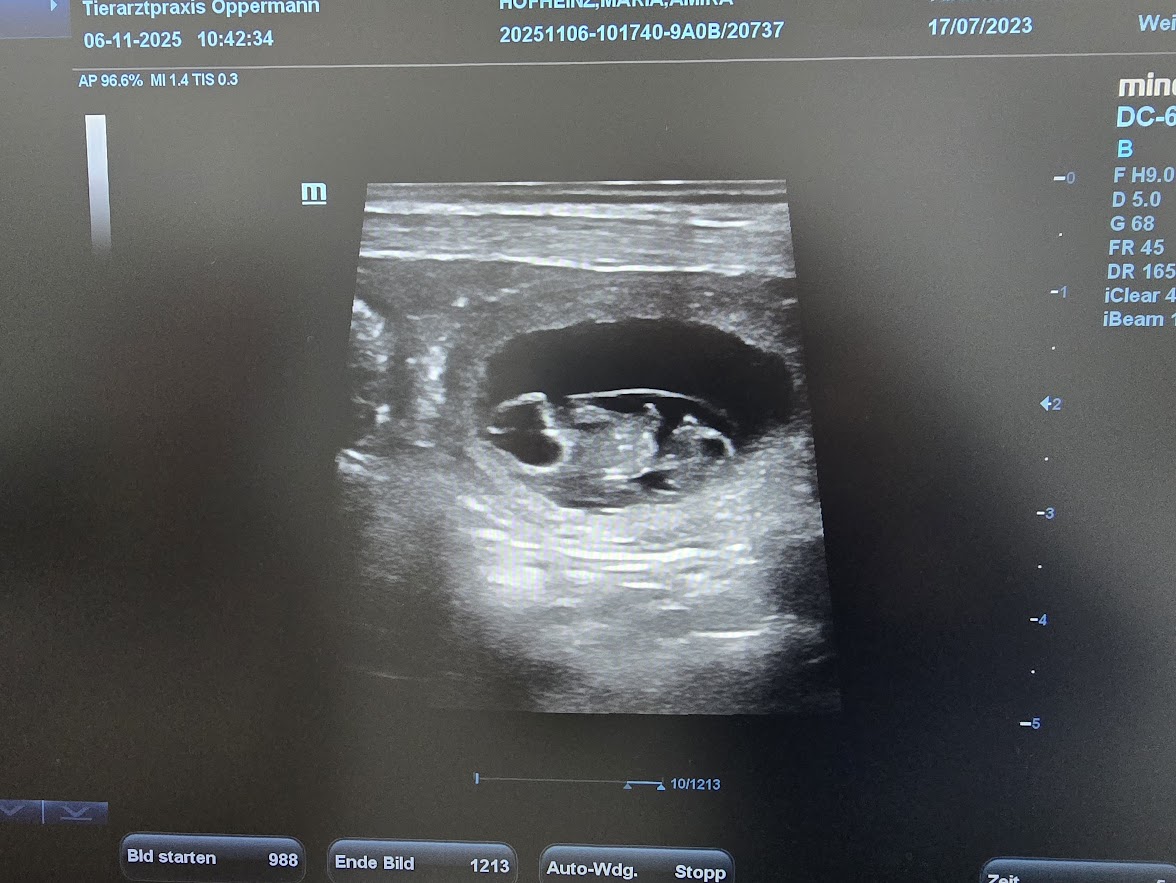

Ultraschalltermin

Voller Aufregung freuen wir uns auf den 06. November! Amiras Ultraschalltermin steht an.

Die Freude ist riesig und wir können mitteilen, dass es im Dezember bei uns Welpen gibt.